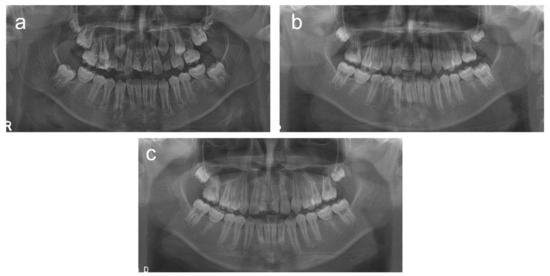

2. Cases

2.1. Case 1

2.2. Case 2

2.3. Case 3